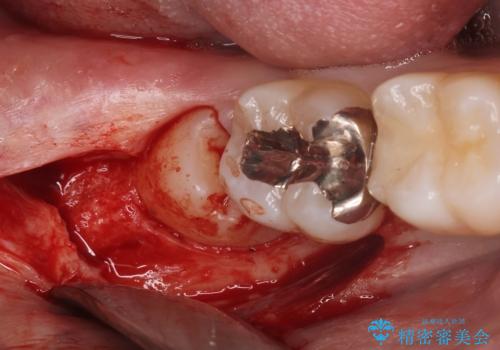

- 親知らずが痛くて抜きたいと来院。

CTを撮影し、神経の位置など確認し安全なことを確認して抜歯を行いました。

抜歯は当日行う事が出来ます。